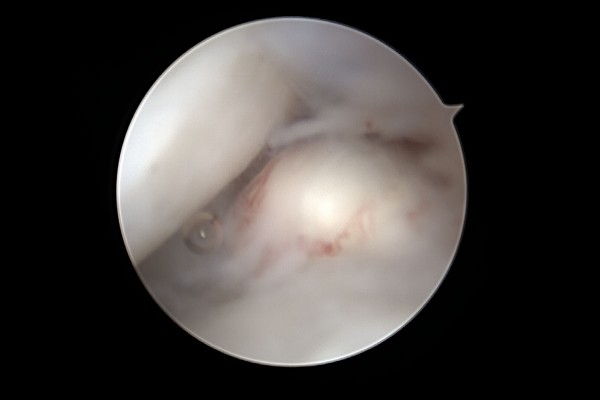

30ec6ec96c3e395fd52bc2174c5bac54_1768985216_4414.jpg

관절내시경 화면을 보면 볼록 튀어나온 석회가 확인됩니다.